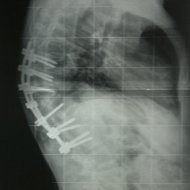

Omurga veremi sonucu kifoz oluşan hastanın ameliyat öncesi ve sonrası filmleri: